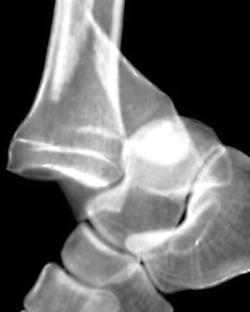

(Слева) При рентгенографии голеностопного сустава в передне-задней проекции определяется латеральный вывих подтаранного сустава. Латеральное смещение пяточной кости указывает либо на ее вывих, либо на ее перелом. Чтобы отличить вывих от перелома, необходимо выполнить рентгенографию еще и в боковой проекции.

(Справа) У этого же пациента при рентгенографии голеностопного сустава в боковой проекции подтверждается наличие вывиха подтаранного сустава. Задняя суставная поверхность пяточной кости не сочленяется с соответствующей суставной поверхностью таранной кости. Кроме того, выявляется перелом латерального отростка таранной кости. Суставные поверхности таранно-ладьевидного сустава конгруэнтны. (Слева) При рентгенографии голеностопного сустава в передне-задней проекции определяется медиальный вывих подтаранного сустава. Задняя суставная поверхность таранной кости не сочленяется с соответствующей суставной поверхностью пяточной кости.

(Справа) У этого же пациента при рентгенографии голеностопного сустава в боковой проекции визуализируется вывих заднего и среднего отделов подтаранного сустава. Кроме того, выявляются переломы «задней лодыжки» и задней части тела таранной кости. Шейка таранной кости не повреждена. Наблюдается вывих таранно-ладьевидного сустава. (Слева) При рентгенографии голеностопного сустава в передне-задней проекции определяется вывих таранной кости. Ее головка ротирована латерально. Также выявляется перелом медиальной лодыжки.

(Справа) У этого же пациента при рентгенографии голеностопного сустава в боковой проекции визуализируется вывих таранной кости относительно всех суставных поверхностей. Перелом таранной кости отсутствует. В некоторых случаях таранная кость вывихивается наружу, повреждая кожные покровы.

2. Рентгенография при вывихе таранной кости:

• Изолированный вывих подтаранного сустава при рентгенографии может быть заметен слабо:

о Отсутствие конгруэнтности

о Частичное перекрытие теней таранной и пяточной костей при рентгенографии в боковой проекции

о Ротация таранной кости относительно большеберцовой и пяточной костей

• Симптом «обнажения суставной поверхности»:

о Суставная поверхность таранной кости видна, однако не сочленяется с пяточной костью

• В редких случаях наблюдают вывих таранной кости относительно всех суставных поверхностей